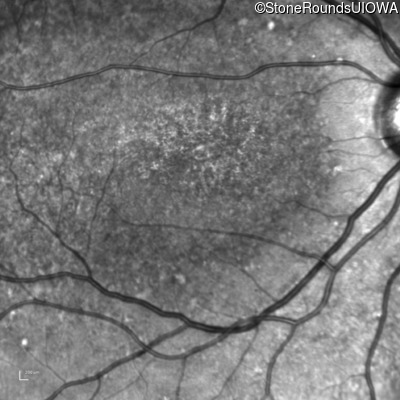

This 16 year old female first had difficulty seeing the blackboard at age 9. Her eye doctor at the time felt at the time that she was "faking it". More recently her eye doctor told her she would be blind by age 20 and suggested she get a seeing eye dog.

| AR Stargardt Disease | ABCA4 | Asp507Tyr GAT>TAT | IVS40+5 G>A | AR |